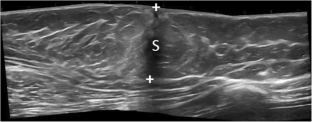

Welch ST, Babcock DS, Ballard ET (2004) Sonography of pediatric male breast masses: gynecomastia and beyond. Pediatr Radiol 34:952–957

Draghi F, Tarantino CC, Madonia L, Ferrozzi G (2011) Ultrasonography of the male breast. J Ultrasound 14:122–129